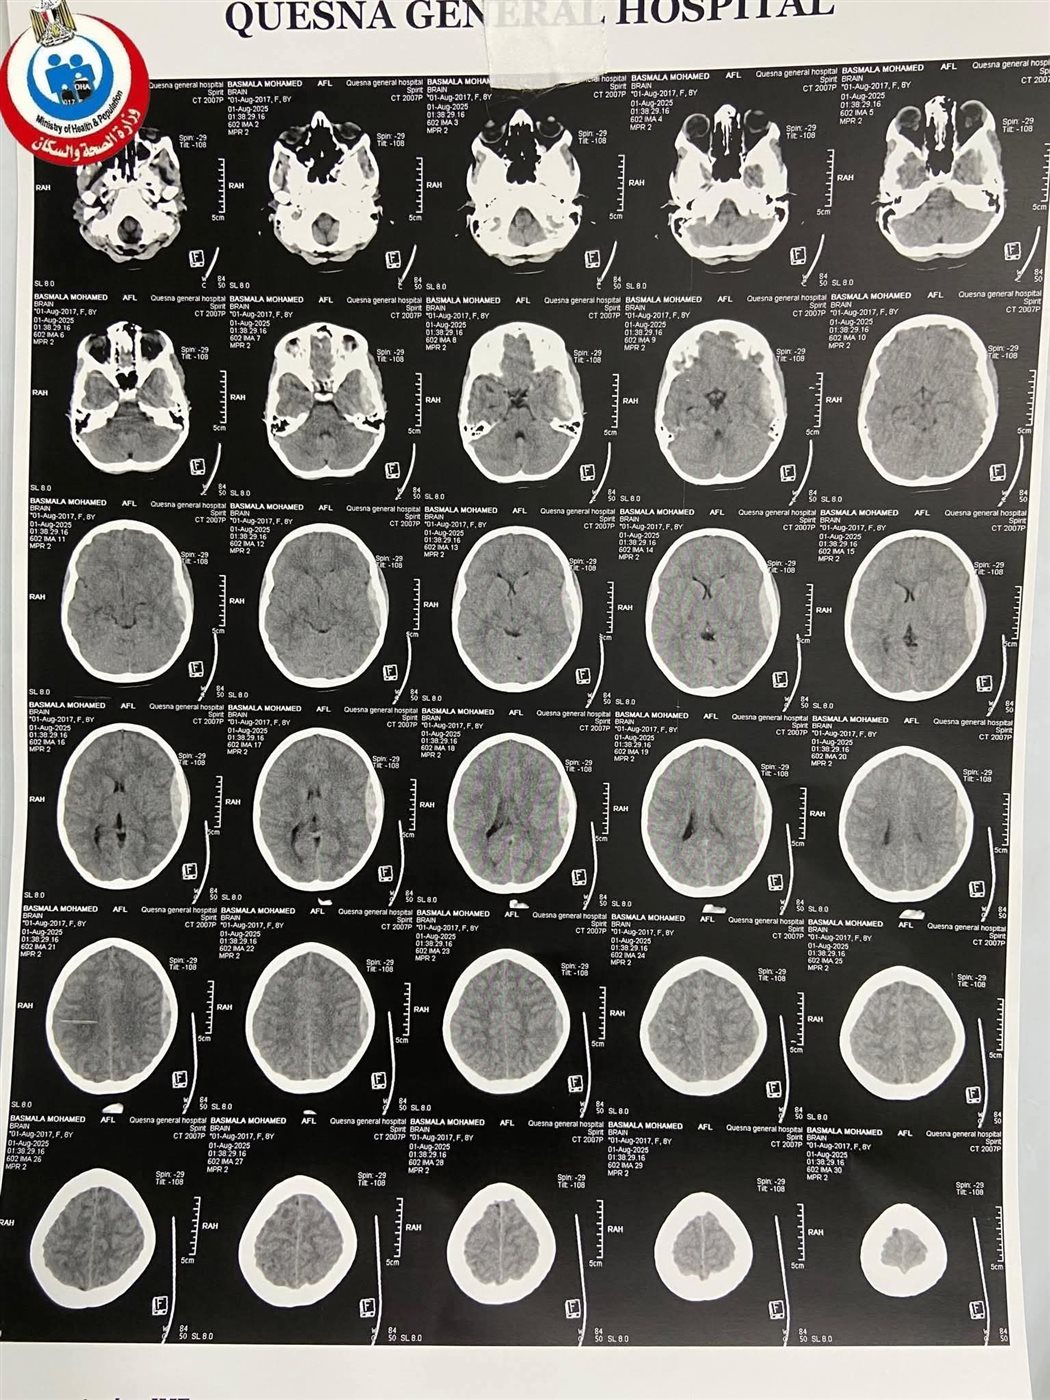

وبالفحص الطبي وإجراء الأشعة المقطعية تبين وجود نزيف داخلي الجمجمة من نوع Extra Dural Hematoma (نزيف فوق الجافية)، ما استدعى التدخل الفوري لإنقاذ حياتها.

عقب العملية، أُجريت أشعة مقطعية ثانية أكدت نجاح التدخل واستقرار الحالة، والطفلة الآن في وعي كامل ومحجوزة تحت الملاحظة الدقيقة بقسم عناية الأطفال.